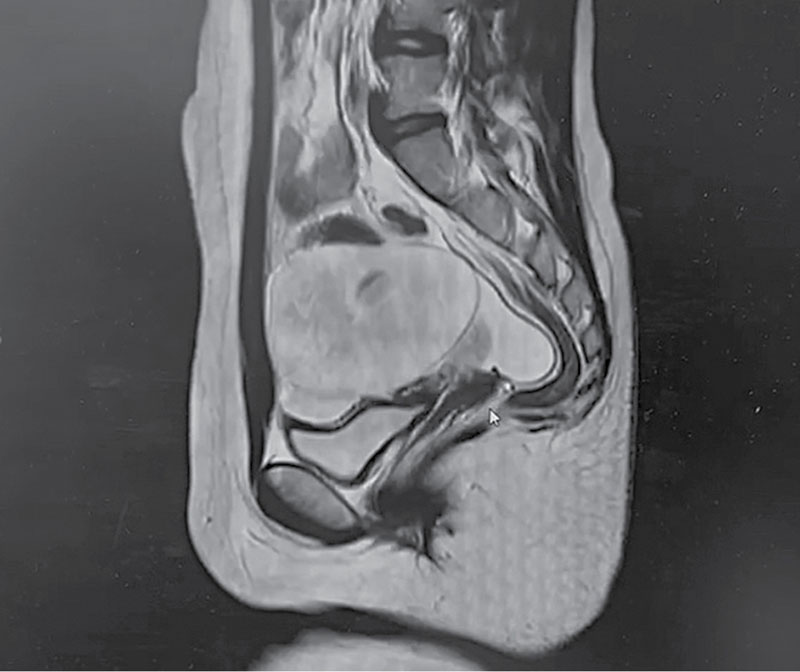

Рис. 2. МРТ ОМТ пациентки А., 11 лет: объемное образование в проекции левых придатков матки

Рис. 5. МРТ ОМТ пациентки В., 13 лет: объемное образование в проекции правого яичника

В сентябре по результатам МРТ ОМТ зафиксировано в позадиматочном пространстве слева образование неправильной формы размером 92 × 70 × 61 мм с нечеткой визуализацией ткани яичника (рис. 2). Кроме того, обнаружена свободная жидкость в полости таза. Заключение МРТ: геморрагическая киста слева.

По данным УЗИ ОМТ, выполненного в стационаре, выявлено объемное образование в области малого таза. МРТ ОМТ показала кистозно-солидное образование в правом яичнике с геморрагическим компонентом и мультифолликулярную структуру левого яичника (рис. 5). Анализы крови на онкомаркеры были в пределах возрастной нормы. Врачи приняли решение направить пациентку в РДКБ – филиал РНИМУ им. Н.И. Пирогова для дальнейшего обследования и лечения.